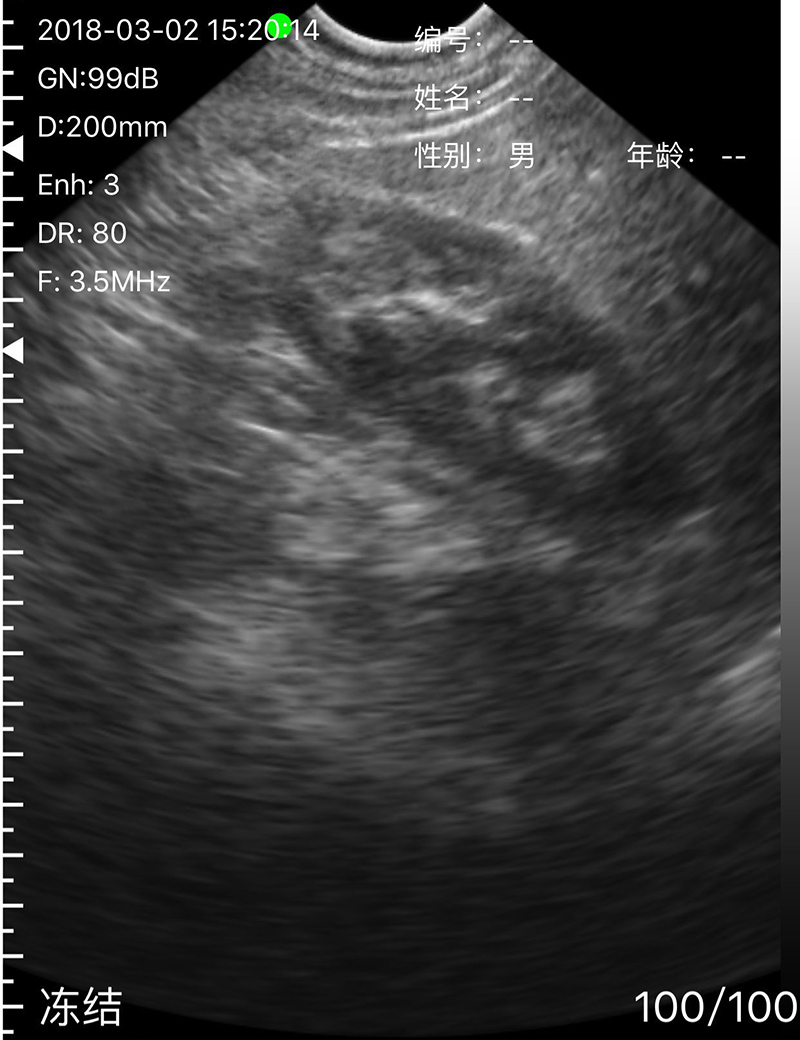

• 显示模式:B、B/M、Color、PW、PDI

• 穿刺辅助功能:平面内穿刺引导线功能,平面外穿刺引导与血管自动测量功能,针尖显影增强功能